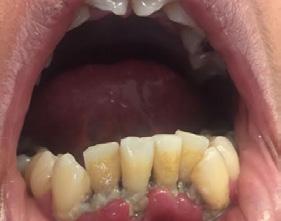

Paciente de 4 años y 8 meses, femenino que se presentó acompañada de su madre para valoración y consulta, presentando dentición mixta y movilidad clase 3 en el diente 71 y caries en diente 72, normoclusión molar y mordida cruzada anterior (Figura 1). Se realizó el plan de tratamiento integral, señalando la necesidad de llevar a cabo la exodoncia y la restauración. Dada la característica clínica presentada, se le conminó a la madre a atender ortodóncicamente a

Figura 1. Figura I. Exodoncia del 71 y caries proximal en diente 72.

la niña de manera próxima inmediata, la cual refirió solo la asistencia para la atención de la exodoncia del deciduo 71, así como la atención de la caries del deciduo 72. La paciente cooperó adecuadamente catalogándola como Tipo IV (+ +) según la clasificación de la conducta Frankl y Wright.7 Se realizaron ambos procedimientos, acordando programar cita para estudios de ortodoncia tras los tratamientos de rutina. Sin embargo, la madre la presentó nuevamente hasta 8 meses después, señalado que tras “caerse” los dientes 51 y 61 “habían salido mal los nuevos”, confirmando la presencia de las posibles anomalías ya previstas, y con mordida cruzada unilateral izquierda, por lo que se le planteó nuevamente la atención ortodóncica a la cual finalmente accedió.